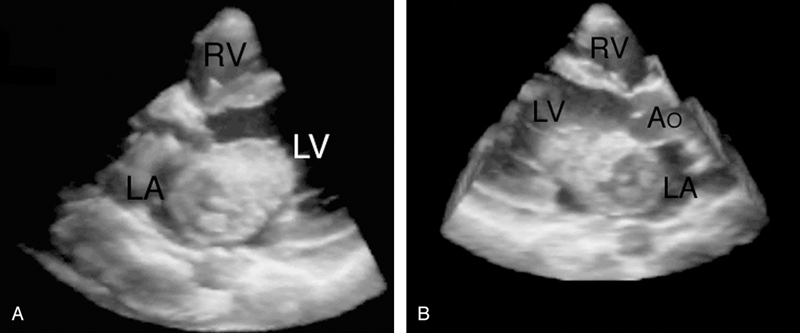

فحوصات تشخيصية لبعض امراض القلب والشرايين التاجية